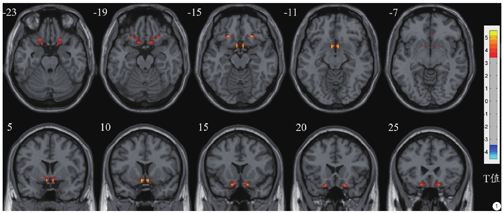

PDM患者较健康对照组VMHC值显著增加的脑区位于双侧膝下皮层和眶额区(峰值=5.5541,体素大小=42),见图1,而未发现VMHC值显著降低的脑区。

与健康对照组相比,PDM患者VMHC值显著增加的脑区位于双侧膝下皮层/眶额区(高斯随机场理论校正,体素水平P<0.001,组水平P<0.05,双侧),未发现此脑区与临床资料存在相关性。